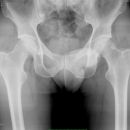

Coxarthrose